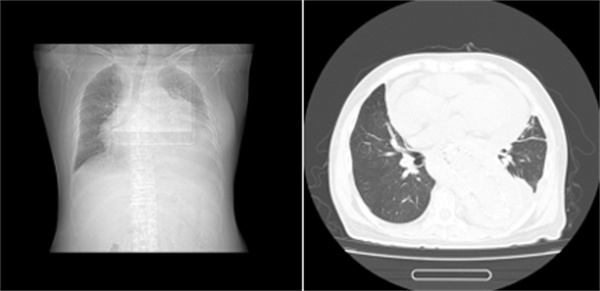

图表1一位长期透析不充分的女性患者

尿毒症毒素会让心包的毛细血管壁变得“千疮百孔”,另外还有尿毒症相关心肌病等问题,毛细血管通透性增加,导致血管里的液体和蛋白质渗出来,堆积在心包腔里。这就像在心脏周围倒了一杯“毒水”,引发了无菌性炎症。

如果水分的摄入(喝水、喝汤、吃水果)没有得到严格控制,多余的水分就会滞留在体内。这部分水不仅会导致腿肿、脚肿、血压高,还会寻找各种缝隙钻进去,会渗到组织间隙,同样也会漏到心包腔里,形成积液。

尿毒症患者各种原因容易出现低蛋白血症。血液中的蛋白质就像“海绵”,能把水分牢牢吸附在血管里。一旦蛋白质减少,“海绵”吸水的功能就下降了,血管里的水分就会跑到血管外,心包就是其中一个“落脚点”。

也就是我们常说的“围透析期”,通常发生在刚开始透析,或者透析不充分的患者身上透析不充分,我们图中第二例患者就是一位未及时开始透析的终末期透析患者。如果透析次数不够、时间不足,毒素清除得不够理想,依然会持续刺激心包。